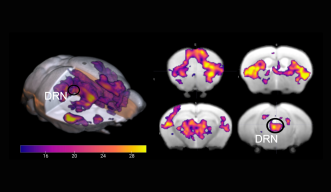

うつ病の3つのタイプを同定 OIST研究者らが、うつ病患者の脳画像などを解析して、一般的に処方されるセロトニン増強薬に反応しないタイプを含むうつ病の3つのサブタイプを同定しました。 2018年10月30日